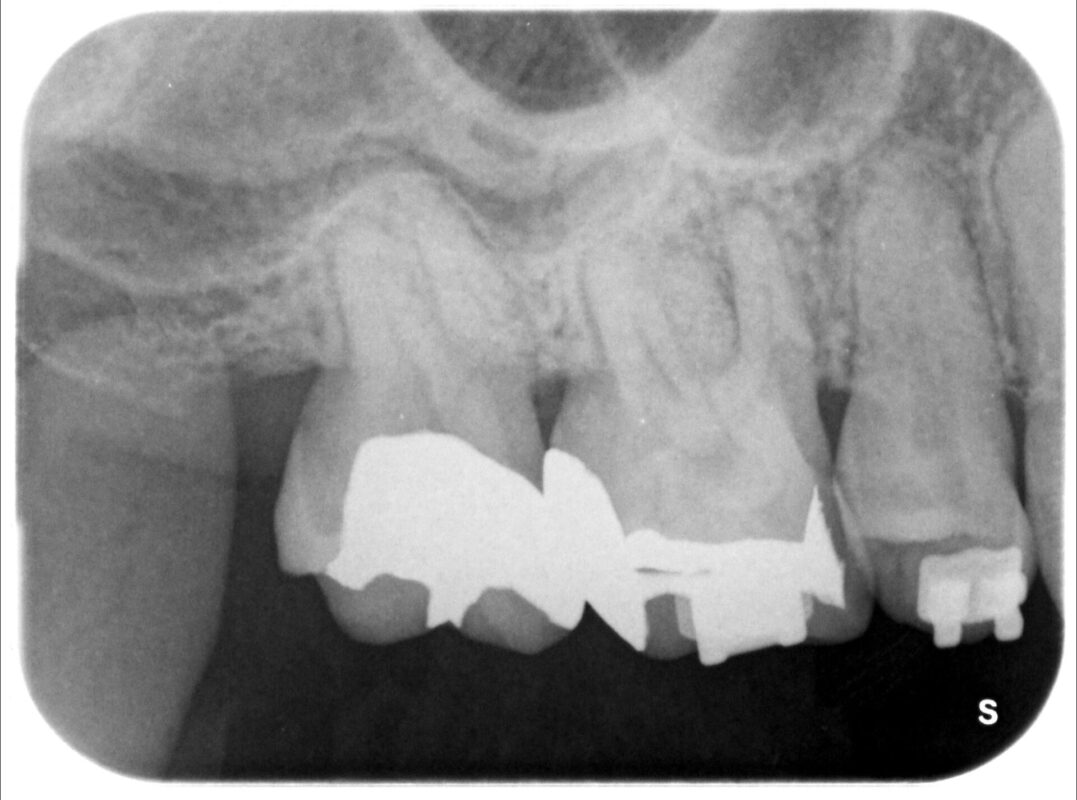

術後2ヶ月目の写真。

分かりにくいですが、歯根分岐部の骨が再生しつつあることが確認できます。

症状は全くなし。